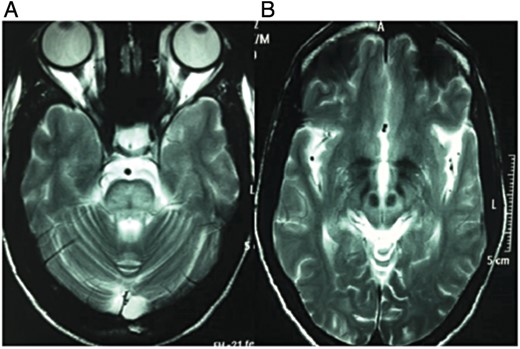

- Diffuse hyperintensities in pons with ‘trident sign’ (Fig. 1, left).

- Symmetrical hyperintensities in both halves of midbrain and periaqueductal gray matter with hypointense red nuclei and subtantia nigra forming ‘face of giant panda’ sign (Fig. 1, right) and hyperintensities in bilateral thalami.

Figure 1:

MRI brain T2-weighted image shows abnormal hyperintensity in pons with characteristic hypointense ‘trident’ sign (A) and characteristic ‘face of giant panda’ sign in midbrain (B).